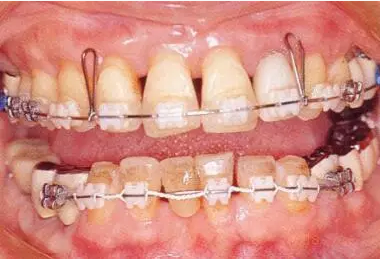

病例7

在正畸治療結(jié)束后仍然存在open contact的病例

在正畸??漆t(yī)生處接受了正畸治療,雖然上頜正畸治療已經(jīng)完成,但由于磨牙區(qū)的邊緣嵴不整齊而導(dǎo)致牙體之間存在空隙。要想在這個(gè)狀態(tài)下護(hù)理牙周組織以及咬合狀況是非常困難的。由此可見,在治療時(shí),正畸??漆t(yī)生與全科口腔醫(yī)生保持目標(biāo)一致是非常重要的。